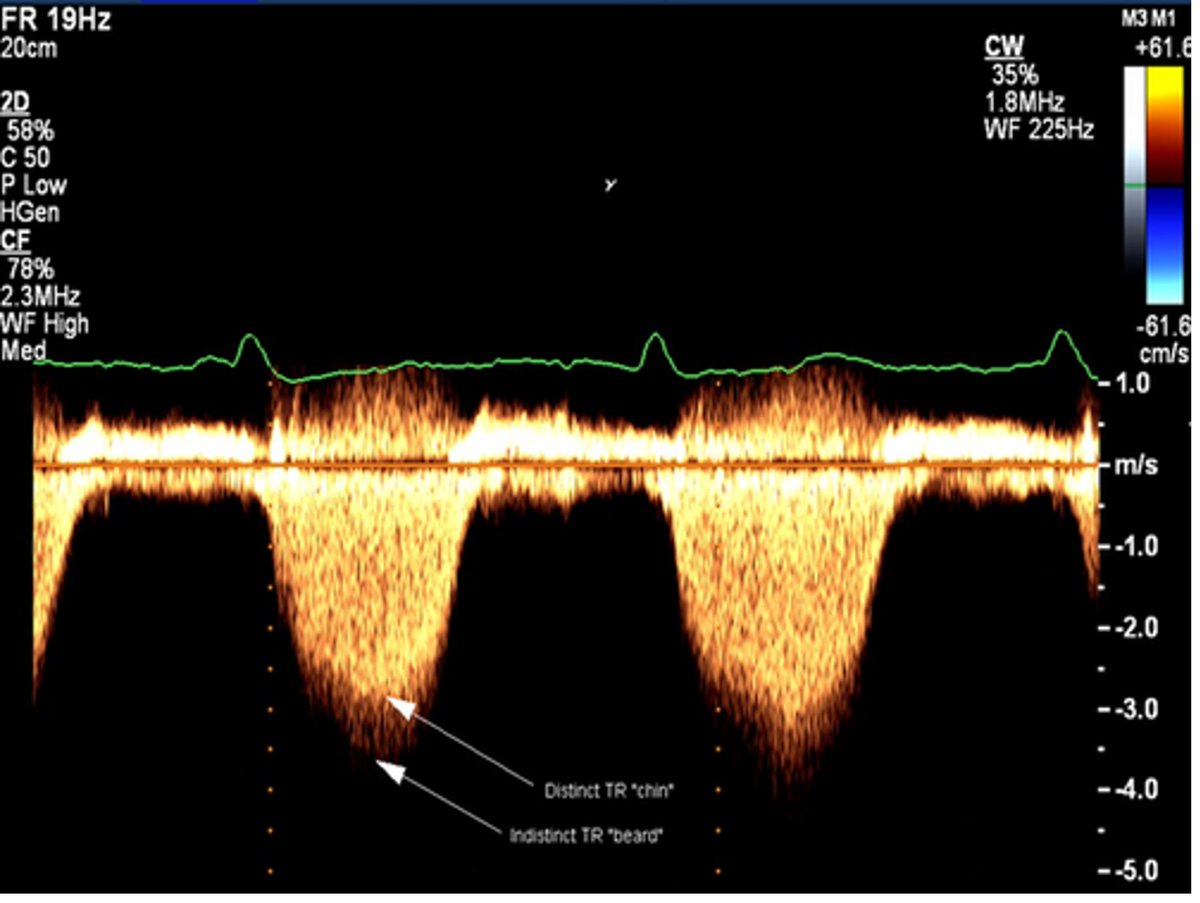

🫀NEW GUIDELINE🫀 Read our newest #ASEGuideline, "Clinical Applications of Strain Echocardiography," developed in collaboration with the European Association of Cardiovascular Imaging of the @escardio! https://t.co/cbZg6KbbX0